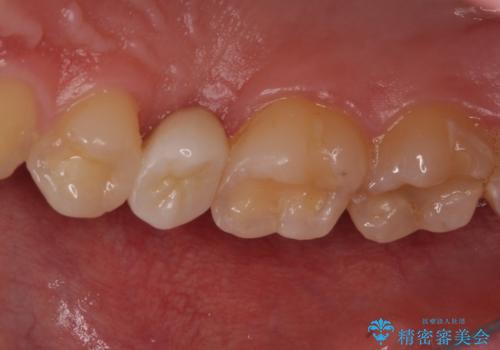

右上もう1本と左上は虫歯治療(セラミックインレー、セラミッククラウン)を行いました。

歯を引っ張り出したり、歯肉の手術の経過待ちの間に、患者様のご希望で他の歯の虫歯治療も行いました。

痛いところがなくなり、患者様には大変満足して頂きました。

・十分に引っ張り出した後、歯肉の手術が必要となります。

・歯肉が落ち着いてから最終的な被せものの製作となります(約3か月)。